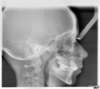

Téléradio Profil